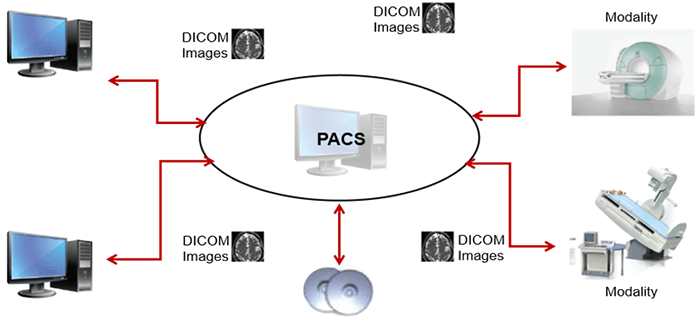

It is important to recognize the acronyms for terminology used when discussing Informatics. Biomedical Informatics (BMI) refers to platforms that are used for medical purposes such as patient care. A picture archiving and communication system (PACS) denotes a BMI platform which is configured in a manner that facilitates storing, retrieving, and distributing medical images.

Here we can see the work organization after the RIS-PACS integration. In fact, PACS is used by radiology personnel to manage the workflow of patient exams:

Operation

This simplified diagram indicates the image data flow between the imaging modality and PACS.

PACS is usually an integration of input from digital devices which may be any radiological modality. These devices include Image acquisition device, image storage server for short or long term storage of data, transmission network, display station, imaging work station, and user interface, camera to convert to hard copies images on a need basis, and integration to radiology information system and hospital information system.

Acquisition

This simplified diagram indicates the image data flow between the imaging modality and PACS.

- Flow: Modalities -> PACS

The flow of “raw” format images. Acquisition protocol for each modality (automation and technologist dependent).

DICOM

DICOM is the international standard used to transmit, store, retrieve, print, process, and display medical imaging information. It involves the integration of image-acquisition devices, PACS, workstations, VNAs and printers from different manufacturers. DICOM is an acronym for Digital Imaging and Communications in Medicine and originated in 1983. It was developed and is maintained to meet the evolving technologies and needs of medical imaging today. It is free to download and use by institutions.

PACS

A picture archiving and communication system (PACS) is a medical imaging technology that provides economical storage and convenient access to images from multiple modalities. The universal format for PACS image storage and transfer is DICOM (Digital Imaging and Communications in Medicine). Combined with available and emerging web technology, PACS can deliver timely and efficient access to images, interpretations, and related data. PACS is used by radiology personnel to manage the workflow of patient exams.